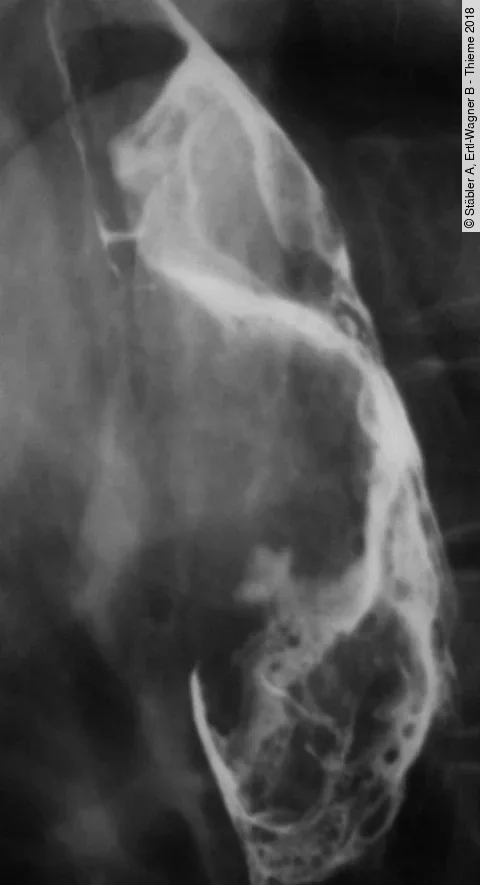

QuizAuflösung: 68-Jähriger mit Schluckbeschwerden

Der Patient hat ein Leiomyosarkom des Ösophagus.